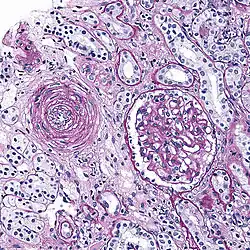

Hyperplastic arteriolosclerosis

This is a type of arteriolosclerosis involving a narrowed lumen.[4] The term "onion-skin" is sometimes used to describe this form of blood vessel[14] with thickened concentric smooth muscle cell layer and thickened, duplicated basement membrane. In malignant hypertension these hyperplastic changes are often accompanied by fibrinoid necrosis of the arterial intima and media. These changes are most prominent in the kidney and can lead to ischemia and acute kidney failure. In the brain, a small cavity called a lacune is an ischemic cavity that can arise due to brain necrosis, due to arteriolosclerosis.[15][16]